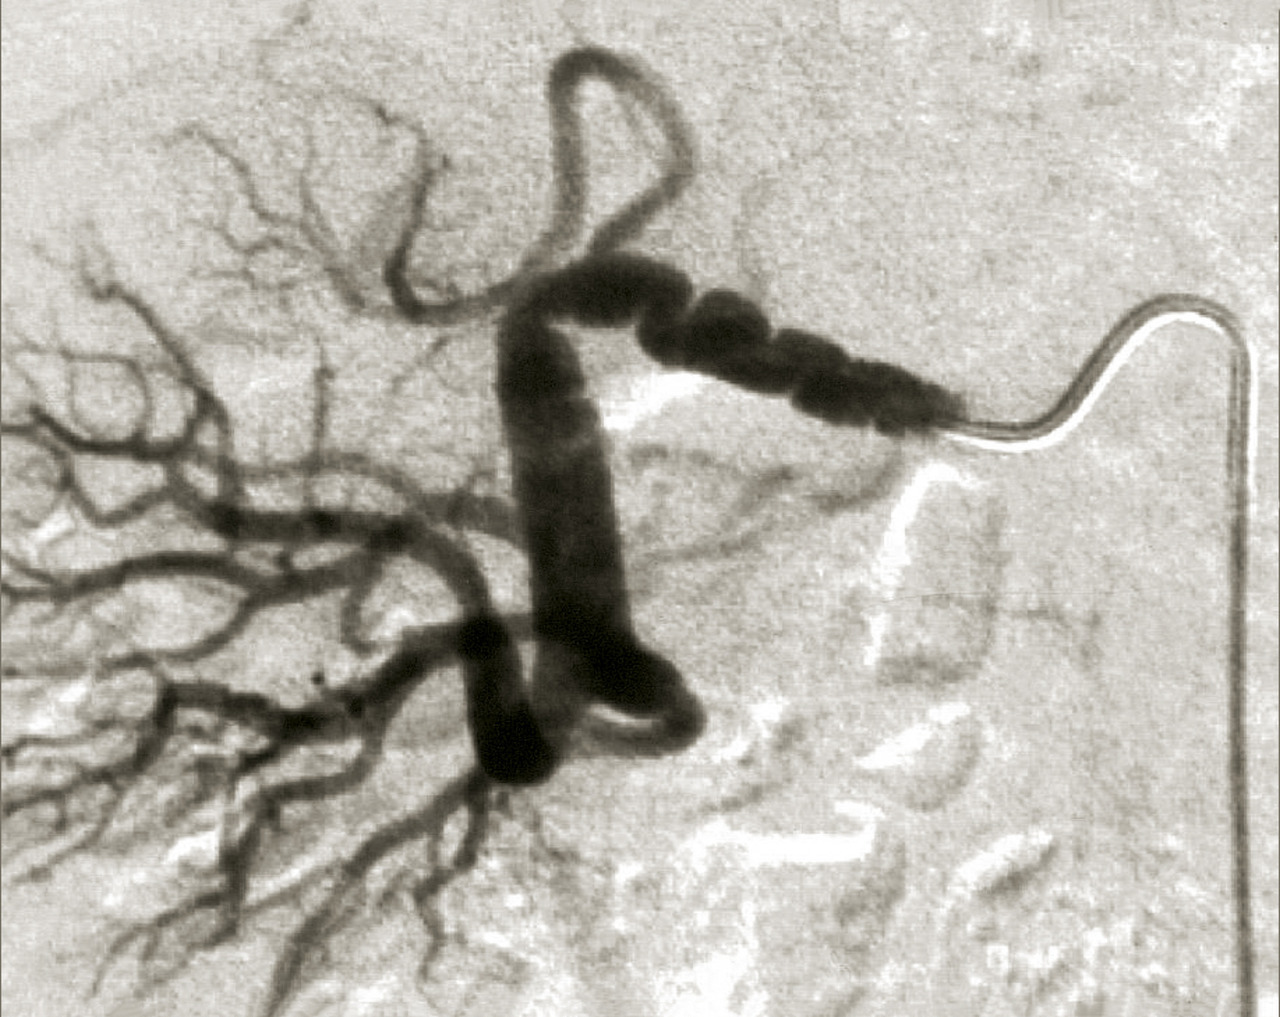

Le tableau résume les avantages et inconvénients respectifs des 3 examens de référence. L’artériographie est réservée aux revascularisations (fig. 4), et n’a pas de place à titre diagnostique.

En cas de fibrodysplasie, les lésions sont multiples, distales, souvent bilatérales, avec aspect en « collier de perles » (fig. 4). Il est recommandé, dans cette pathologie qui est souvent multifocale, de rechercher d’autres lésions artérielles (sténoses ou anévrismes) au niveau des artères digestives, cervicales et intracrâniennes.